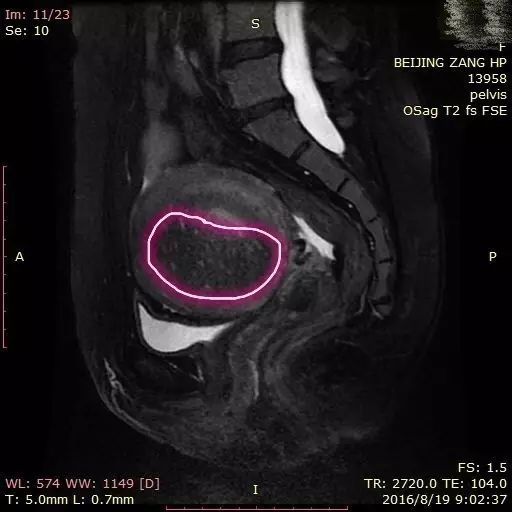

她有强烈的保留子宫的愿望,B超提示她子宫壁有回声不均,可能是子宫肌腺症的情况。经过核磁共振的检查,我们进一步明确的她的病灶范围,从图1和2可以看到他的子宫前壁明显增厚了,和正常后壁仅有2cm左右的肌壁内相比较,增厚了整整一倍,而且里面星星点点,布满了出血以后导致的亮点。这次来月经的时候,这些亮点的病灶部位也会跟着出血,和宫腔出血不同,这些血无法排出来,就会导致严重的疼痛。

在今年8月29日我们对她实施了这次治疗,治疗前,我们画出了病灶所在的范围(图4、图5),然后智能的计算机根据我们所画的病灶范围以及标定出来的危险区域,自动帮我们设置了这些绿色的需要治疗的靶区,共规划出79个点(图6)。